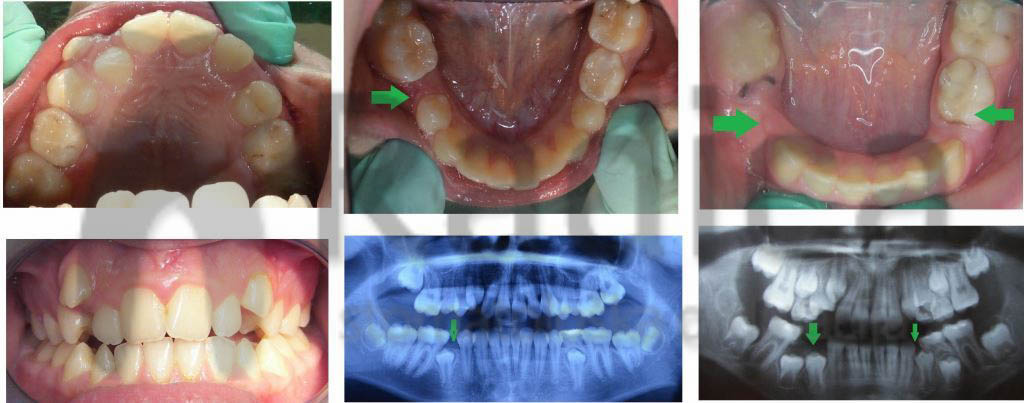

Prerano izgubljen mliječni zub uzrokuje gubitak mjesta za trajnoga nasljednika. Stoga nastaje gužva ili čak neki zubi nemaju gdje niknuti pa ostaju u kosti – nastaje anomalija koju nazivamo sekundarna kompresija.

Najčešće su to zubi koji se zadnji pojavljuju u čeljusti – gornji očnjaci i donji drugi premolari – „petice“.

U sljedećim primjerima su pokazani takvi slučajevi: